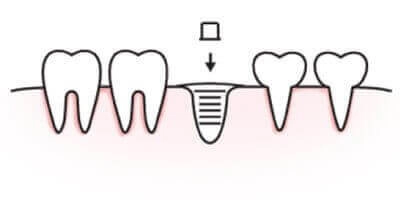

01. 放入植體

局部麻醉下進行翻辦,準備植體所需空間,放入植體與牙齦塑形螺帽。

人工植牙